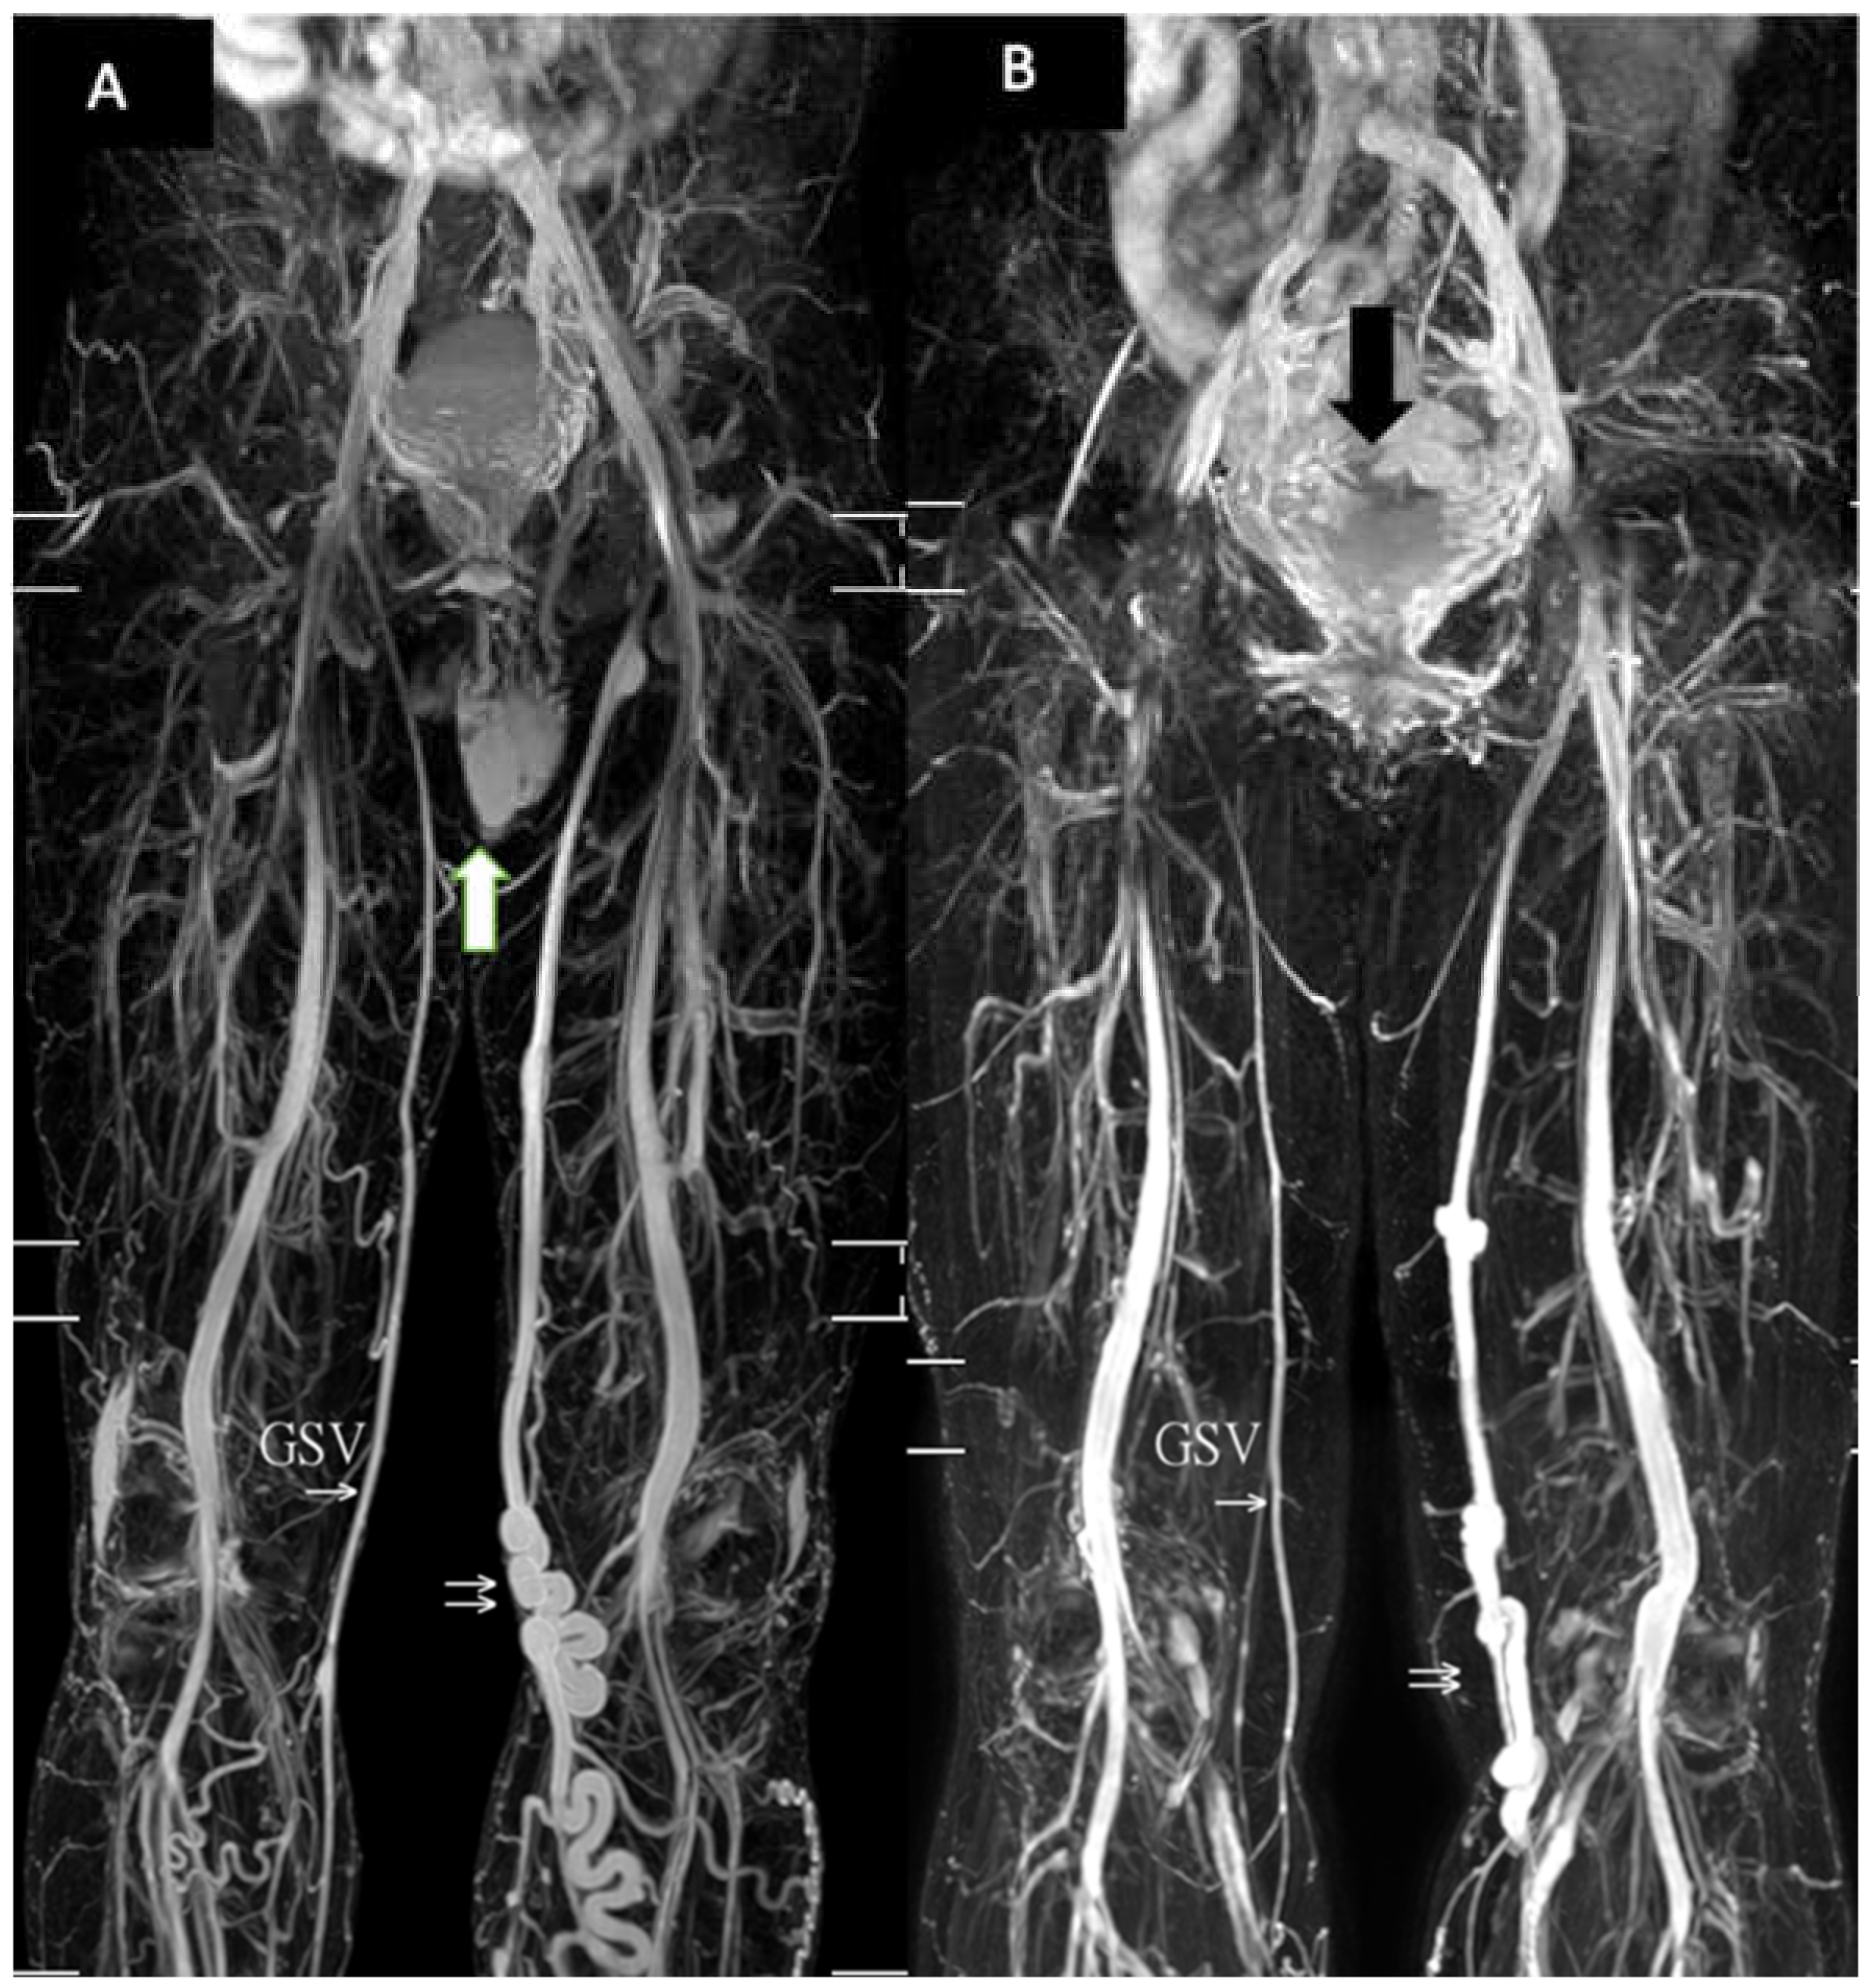

| GSV | great saphenous vein |